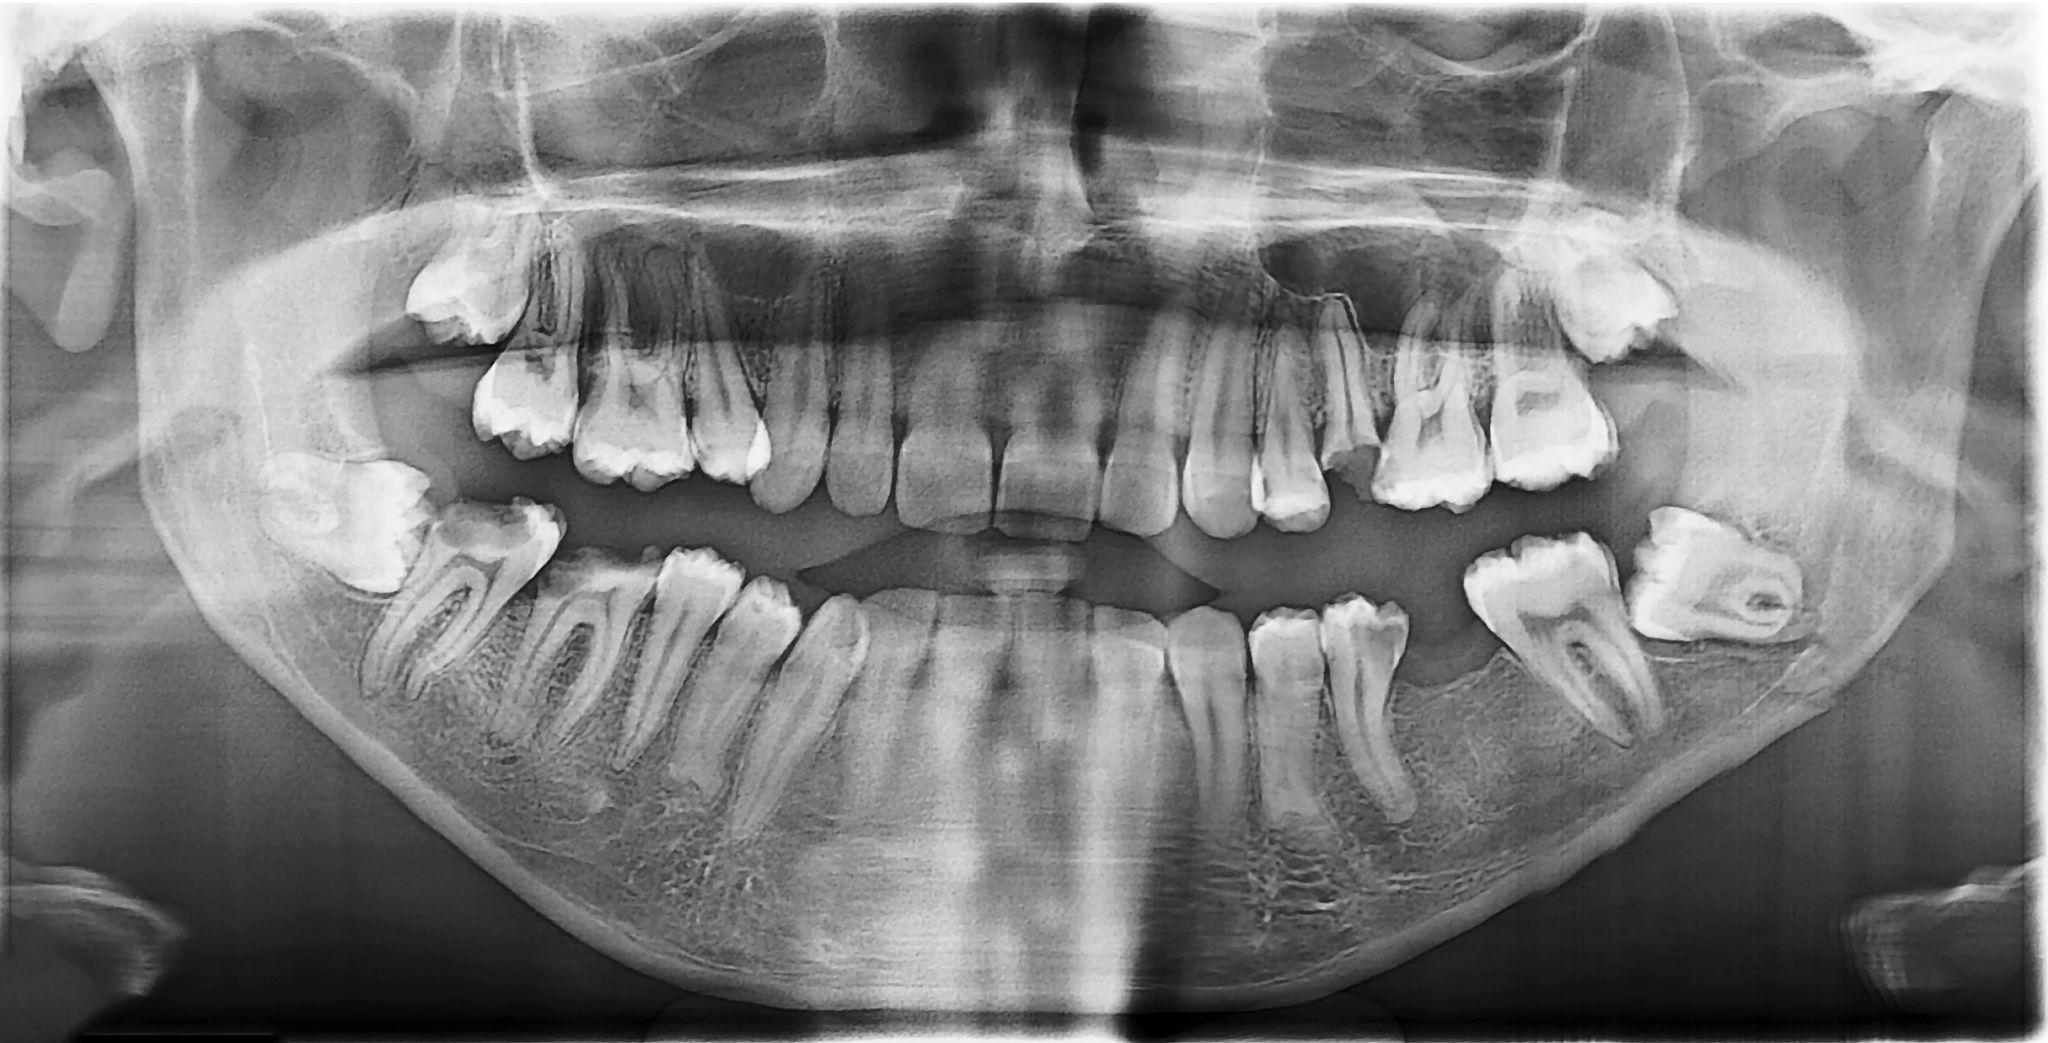

Gömülü 20’lik Diş Çekimi Daha mı Ağrılıdır?

Evet. Gömülü dişlerde:

- Kemik dokusu kaldırılabilir

- Dikiş atılabilir

- İşlem süresi uzayabilir

Bu nedenle iyileşme süresi basit çekimlere göre biraz daha uzun olabilir. Ancak doğru cerrahi teknik ve uygun bakım ile süreç kontrollü ilerler.